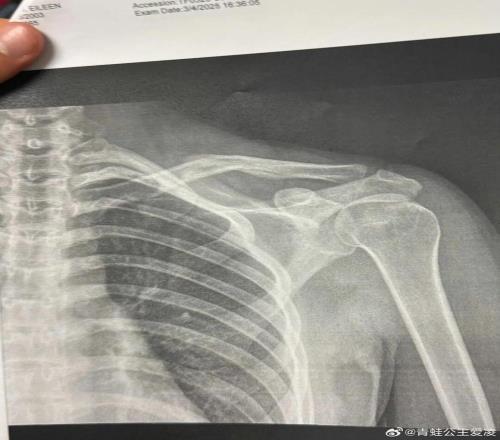

2025年是谷爱凌口中“职业生涯最困难的一年”,三月她在阿斯本练习中遭受严峻的脑震荡,导致急性颅内出血、癫痫发生,一度失掉认识五分钟,如此严峻的伤病让她一度以为自己再也醒不过来。八月的意外受伤让她错过了亚冬会,十一月复出后的失利又引发外界的质疑,种种猜想都让她的心思得到深入的锻炼。